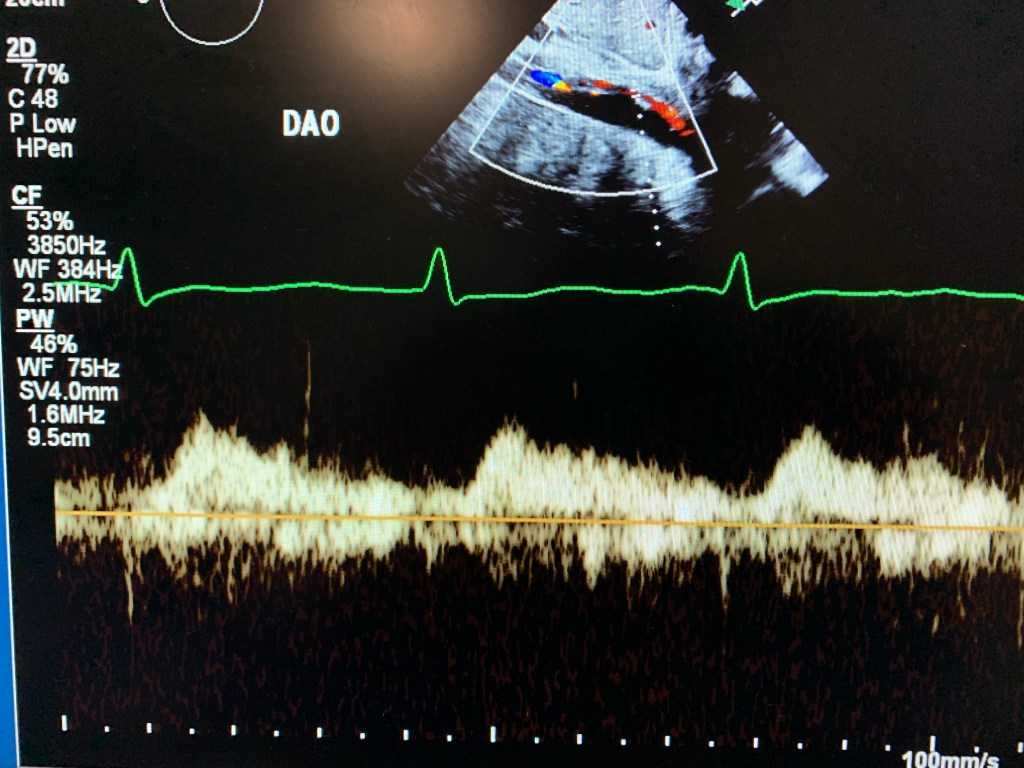

Echo:

Visualize PLAx view. Use high window and color Doppler.

Subcostal and suprasternal. Especially descending aorta.